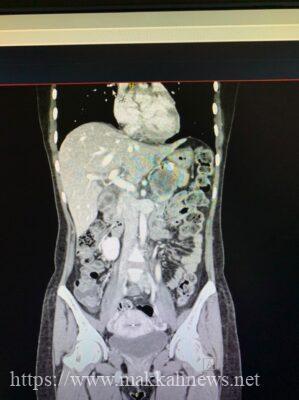

واستقبلت المدينة الطبية المريضة والتي كانت تعاني من ارتفاع دائم لضغط الدم وتم عمل عدد من الفحوصات الطبية اللازمة والاشعة المقطعية والتي اظهرت نتائجها وجود مايسمى بورم القواتم في كلتا الغدد الكظرية بالجانبين اضافة الى ورم بالغدة الدرقية وورم آخر ممتد الى الفص الايسر من الكبد كما تبين وجود ارتفاع في نسبة هرمون الكالستونين والادرينالين والنورادرينالين. حيث تم اخذ خزعة من ورم الغدة الدرقية والذي تبين انه من النوع الخبيث.